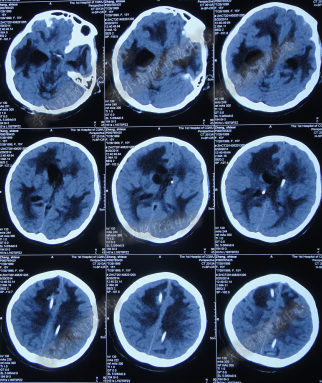

第3次手术右侧脑室外引流术后1个月时间内,脑积水仍没有得到控制,再给予腰大池引流,期间多次试图拔除右侧脑室外引流管(多次调高脑室外引流管的高度),但因患者意识变差,而无法拔除引流管,给予拔除腰大池引流,治疗期间曾多次查头部CT均示脑积水仍无改善(图-20、图-21、图-22、图-23)。

图-20:2014年7月24日头部CT

图-21:2014年7月29日头部CT

图-22:2014年8月4日头部CT

图-23:2014年8月15日头部CT